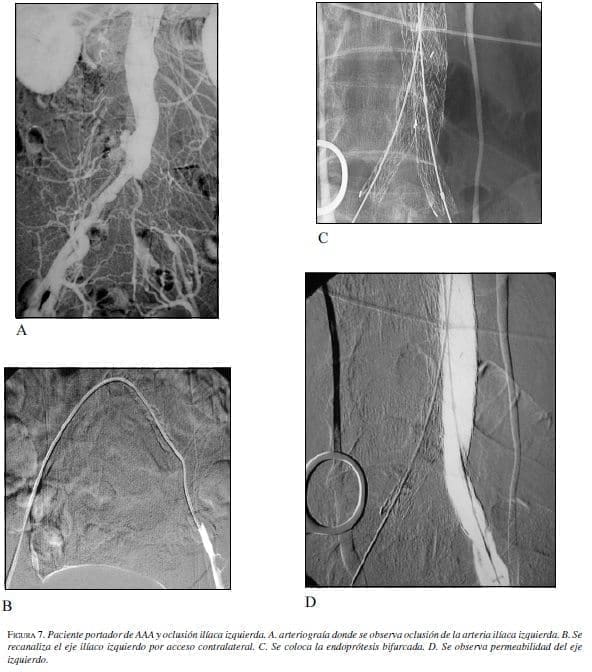

Se describe esta técnica más adelante en este artículo. En casos de oclusión completa de un eje ilíaco, se puede intentar su recanalización; cuando ésta resulte infructuosa, se utiliza una endoprótesis monoilíaca y un puente femorofemoral (23).